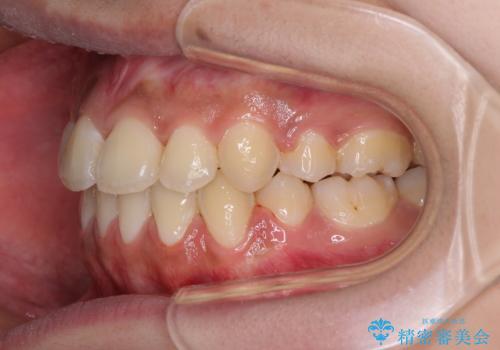

- 八重歯と上下前歯のでこぼこを気にして来院された患者様です。

上下前歯部叢生のスペース獲得のため、上下顎左右小臼歯各1歯(計4本)と全ての親知らずを抜歯して、矯正治療を行うこととしました。

上下の正中位置が大きくずれていたため、治療期間の長期化や正中が合わないまま終了することが予想されましたが、思っていた以上にスムーズに歯が移動し、満足いただける仕上がりとなりました。